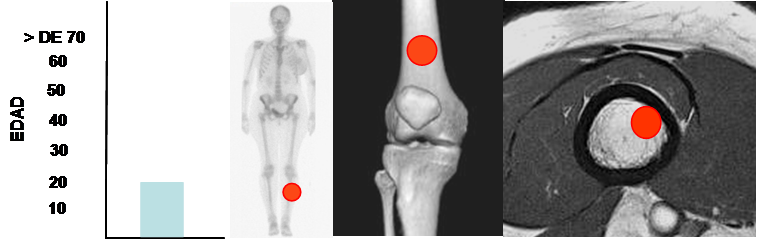

Casi todas las lesiones comprometen la parte anterior de la diáfisis tibial y afecta pacientes en la 1º y 2º décadas. (18). (Fig 105).

Fig 105. Displasia osteofibrosa.

Mayor frecuencia entre 1º y 2º década. Predominio en la tibia.

Lesión diafisiaria, de ubicación excéntrica.